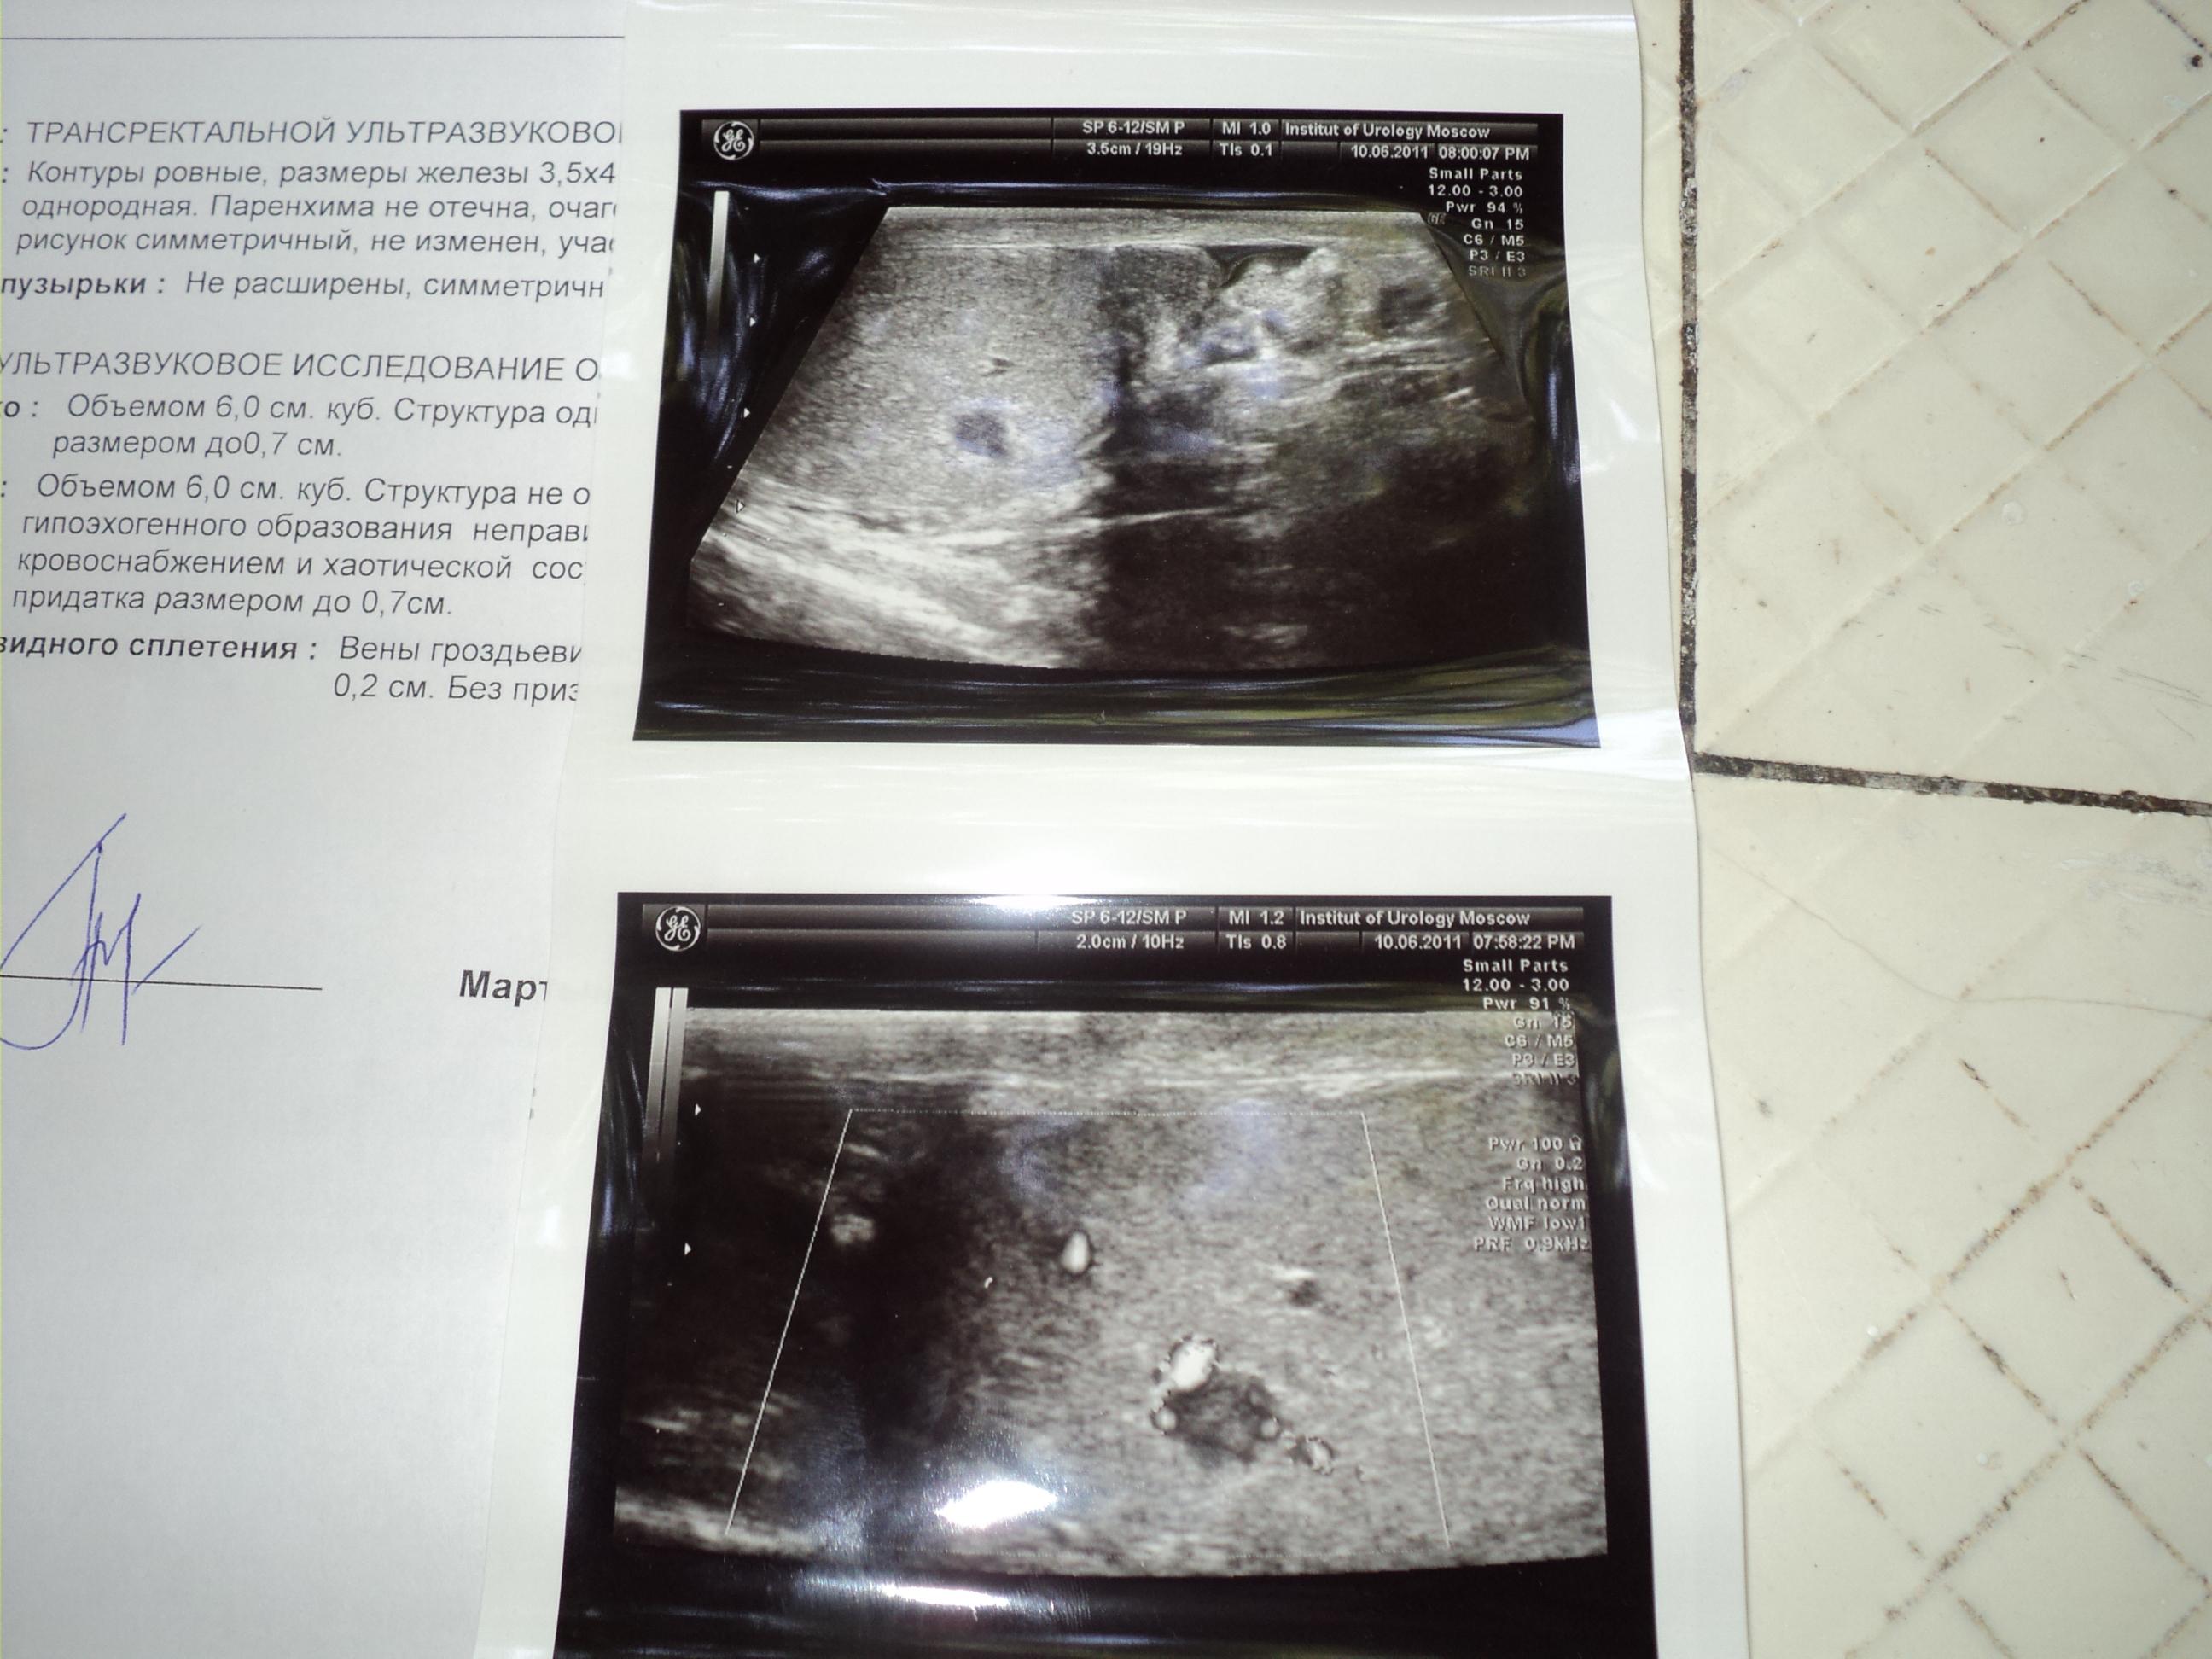

Здравствуйте! Сделал Узи мошонки с допплером: Правое яичко: Объемом 6,0 см.куб. Структура однородная.придаток не увеличен. Головка придатка размером до 0,7 см. Левое яичко: Объемом 6,0 см. куб. Структура не однородная за счет наличия в среднем сегменте гипоэхогенного образования неправильной формы до 0,7 см. с умеренно выраженным кровоснабжением и хаотической сосудистой архитектоникой . Придаток не увеличен. Головка придатка размером до 0,7 см. Вены гроздьевидного сплетения слева при натуживании расширены до 0,2 см. Без признаков ретроградного кровотока.Сдал анализ крови на АПФ(МЕ/мл) результат 3,норма меньше 8. Бета ХГЧ (МЕ/л)-результат 0,норма от 0-8. ЛДГ результат 316,норма от 0-450. Пожалуйста скажите,что это такое? Я очень переживаю!!!